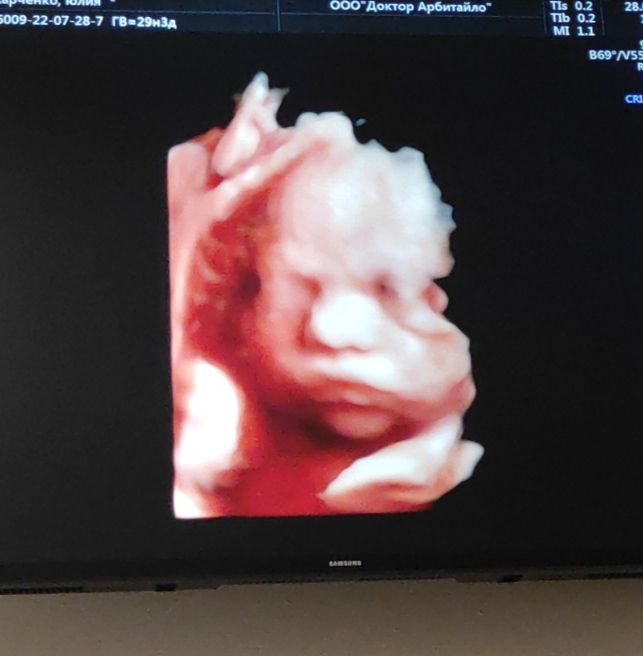

3 скрининг и 3д фото 29 н

Вес 1300г. Поставили срок на неделю меньше по узи, чем по месячным. Сказали, малышка небольшая. Хотя я сама набрала уже 12 кг